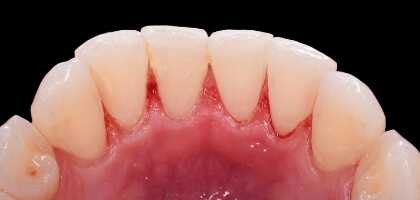

Mantenemos tu la salud bucodental al día, previniendo la aparición de enfermedades. Eliminaremos el sarro que se acumula en las encías o el cuello de nuestros dientes y las manchas, realzando la estética general con una sonrisa limpia, sana y agradable.